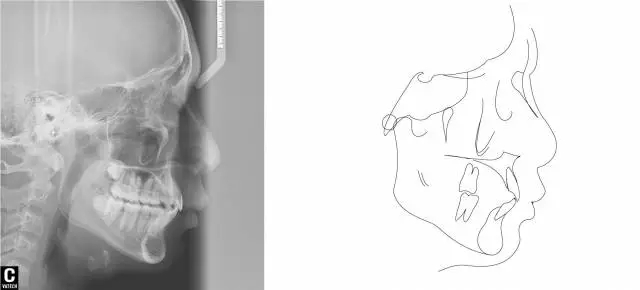

術(shù)后全景,側(cè)位照。

幾何畫板技術(shù)完成術(shù)后頭影測量!

案例隨訪:1.本案例引導(dǎo)下頜向前,術(shù)中1年半期間,前導(dǎo)后咬合關(guān)系始終保持淺覆合淺覆蓋關(guān)系,雙側(cè)關(guān)節(jié)骨重建達1年以上,處于穩(wěn)定狀態(tài),基本達到關(guān)節(jié)骨重建6-8月時間。

2,關(guān)節(jié)健康,無異常!

3.患者積極配合佩戴透明保持器。6個月復(fù)查,無明顯復(fù)發(fā)現(xiàn)象,保持良好!